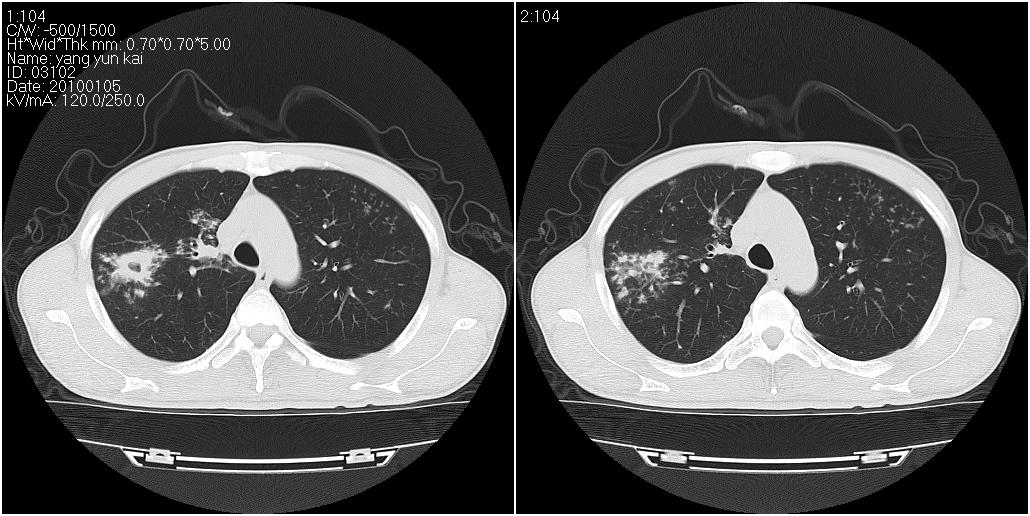

标题: CT23980:男性,47岁。近来咳痰、咳血,血沉增快(40左右),

男性,47岁。近来咳痰、咳血,血沉增快(40左右),痰中未检出结核杆菌。

两肺继发性肺结核并多发性结核球形成,部分病灶内空洞形成。

符合继发性结核表现部分空洞形成并播散